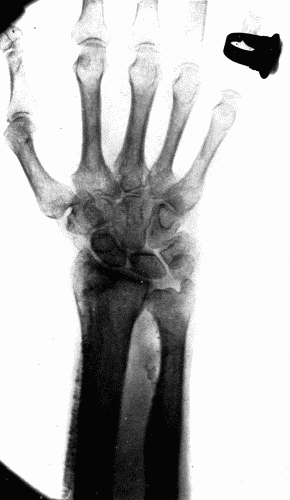

Thus the sclerosis of the radials of such an extent that these arteries are easily palpable, appears to be a different process from that of the sclerosis in the aorta, yet fundamentally it is the same. The difference lies in the anatomic structure of the two vessels, and possibly also in the degree of stretching and strain to which the vessels are subjected at every heart beat. In the radial artery the media as usual is affected first. The muscle cells undergo degeneration and either marked thickening takes place or sacculation results, depending upon the severity of the exciting cause. Calcification of the media is common. This occasionally takes the form of rings encircling the vessel, and gives to the examining finger the sensation of feeling a string of fine beads. There may be calcification of the subintimal tissue without deposits of lime salts in the media, but this is more commonly found in the larger arteries. When the calcification occurs in plates through the media, the well known pipe stem vessel is produced. (Fig. 6.)

Fig. 6.—Radiogram of a man aged seventy-five, showing calcification of both radial and ulnar arteries. Fig. 6.—Radiogram of a man aged seventy-five, showing calcification of both radial and ulnar arteries.